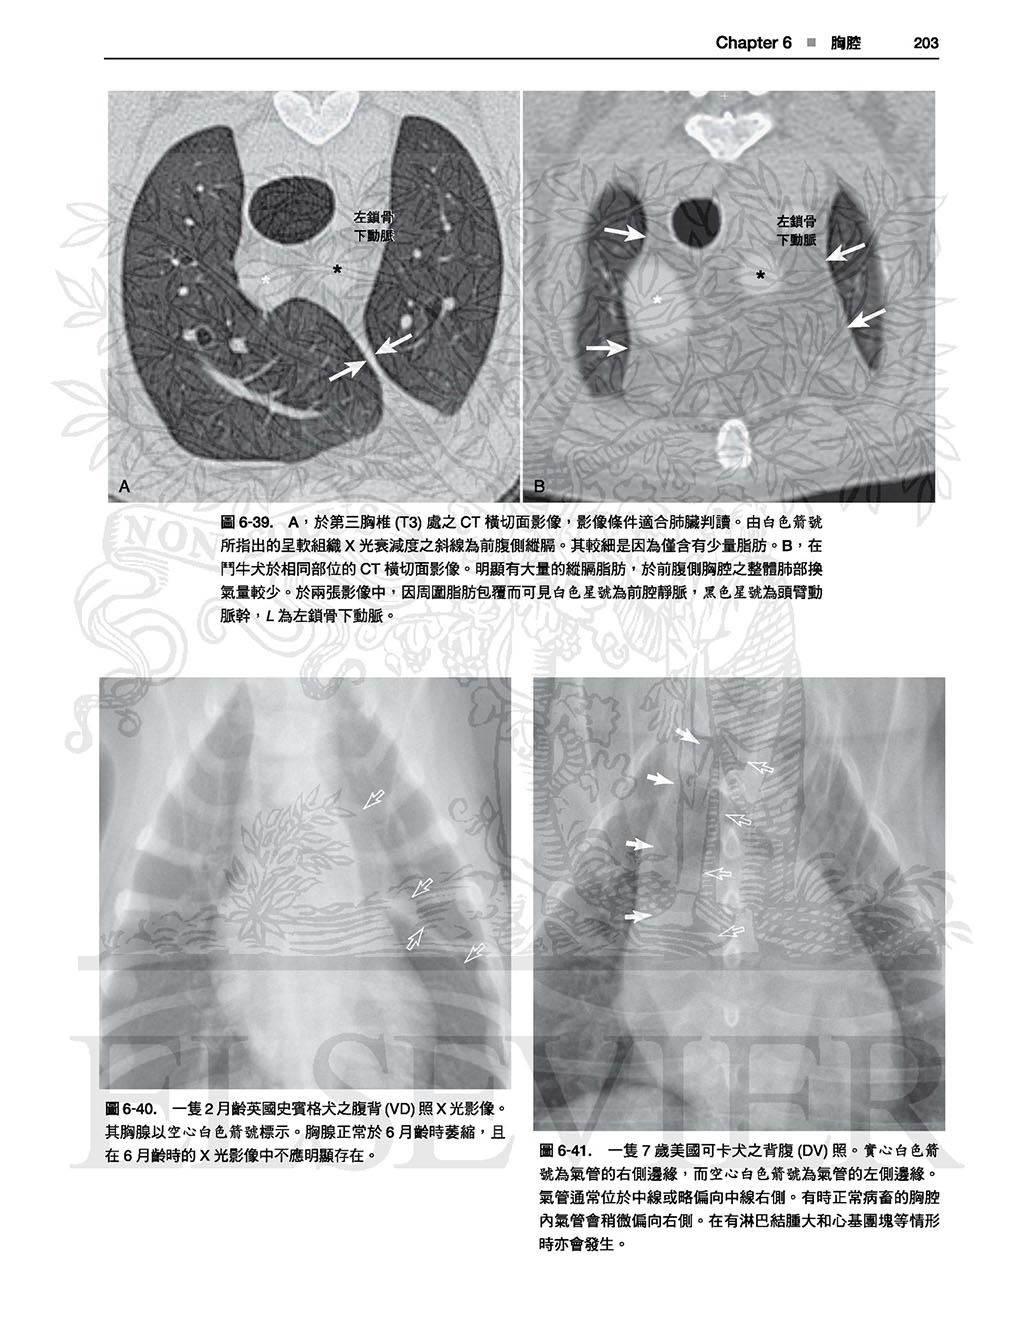

本書並不只是單純的圖譜,各身體部位皆有文字敘述,

因此有助於讀者理解各構造於X光影像學中如此呈現之原因,且提供了讀者對於X光影像學原理基礎性的理解,

有助於對其他正常變異之辨別,雖然可能需要讀者花點心力與圖譜對比使用,但對於判讀能力會有不小的幫助。(本書前言)

以這本詳盡的圖譜學習犬貓正常放射線解剖學的範圍。精通本書將可使診斷更精確並達到更佳的治療效果!

全書皆為高對比的數位影像,除提供正常影像的深入判讀外,亦提供常見且易被誤判為疾病的正常變異;另外並提供多張電腦斷層影像以強調某些結構之影像在放射線學下顯得如此獨特的原因。

本書不但含有豐富圖片,身體各部份皆附上文字描述以協助讀者了解放射解剖學原則,讀者可舉一反三、甚至能以此理解未包含於本書的正常變異。

最新!包含問題、解答及解題的伴讀網站,超過一百個加強重要放射線解剖學觀念及著重於正常差異誤判為疾病的問題。

最新!更多的電腦斷層影像,詳細解釋某些結構形成獨特放射線學影像的原因。

最新!提供更廣泛的正常範圍。

最新!提供各品種犬貓之獨特影像。

.詳盡的文字說明及圖片標示

.未標記的原始圖片及標示後的圖片比對

成為專業放射診斷醫師是一條漫漫長路,需要在考到獸醫師執照後最少再四年的學習及各階段的嚴峻考試才能得到學會的專業認證,但是每天進行X光影像判讀的獸醫師中畢竟是只有少數是學會認證的放射診斷醫師,大部分的X光影像判讀是由相較未受到專業指導及臨床訓練的一般獸醫師執行。如同剛開始發展判讀技巧的學生,這些獸醫師應對正常的X光影像解剖學、解剖差異及看似疾病的影像(這些影像被我們這種花費一生在判讀影像的人暱稱為「假象」(takeout))有深厚的辨識度。犬貓中巨大的正常差異令人瞠目,雖然貓較為一致,但犬則有各種不同的形狀及大小,其中還有各種若無法分辨為正常即可能被誤判為疾病的遺傳性差異。除了遺傳性差異外還有因X光拍攝擺位造成的差異,也可能造成正常結構形成無數的造影差異。於專業訓練中,這些觀念會在無數小時的專人指導及訓練下被深深植入,而另一方面未受專業訓練的獸醫師可能在學校時看過一些正常的X光影像解剖學,但伴隨著其他成為一名合格執業獸醫師需要的大量記誦知識後,這些記憶變得模糊。於在學期間不太可能接觸所有臨床上可能遇見的正常範圍及受到擺位影響的影像,因此臨床獸醫師及學生們確實需要一個X光影像的判讀對照標準以進行適當的臨床X光影像學判讀。本書即因此需求而生。於本書中,我們不只指出了基本上犬貓中所有具臨床意義的解剖構之X光影像,也包含可能影響判讀的解剖構造正常差異的例子,若只是單純地標示犬貓各構造的X光影像對於提供具臨床意義的標準並無幫助。此外本書亦包含了關於唯有放射師 能提供的正常解剖描述之內容:以正常影像如何被拍攝步驟影響的方式呈現,雖然本書並非為X光造影擺位的指南,但因具體的操作因素可能對X光影像的影響極大,故為了能進行精確判讀仍帶有部分相關資訊。

最後,本書並不只是單純的圖譜,各身體部位皆有文字描述,因此有助於讀者 理解各構造於X光影像學中如此呈現之原因,且提供了讀者對於X光影像學原理基礎性的理解,有助於對其他正常變異之辨別,雖然可能需要讀者花點心力與圖譜對比使用,但對於判讀能力會有不小的幫助。

全書皆為高對比的數位影像,除提供正常影像的深入判讀外,亦提供常見且易被誤判為疾病的正常變異;另外並提供多張電腦斷層影像以強調某些結構之影像在放射線學下顯得如此獨特的原因。

本書不但含有豐富圖片,身體各部份皆附上文字描述以協助讀者了解放射解剖學原則,讀者可舉一反三、甚至能以此理解未包含於本書的正常變異。

最新!包含問題、解答及解題的伴讀網站,超過一百個加強重要放射線解剖學觀念及著重於正常差異誤判為疾病的問題。

最新!更多的電腦斷層影像,詳細解釋某些結構形成獨特放射線學影像的原因。

最新!提供更廣泛的正常範圍。

最新!提供各品種犬貓之獨特影像。

.詳盡的文字說明及圖片標示

.未標記的原始圖片及標示後的圖片比對